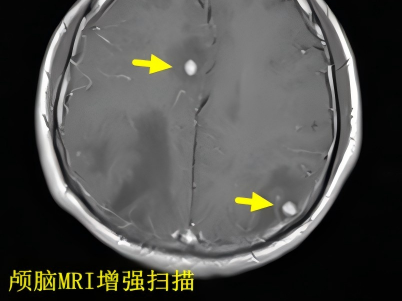

近日,我院神经外科成功完成一例神经导航辅助下的脑深部病变活检手术,为一名疑难病患者明确了诊断方向。 疑难病例 多系统病变待确诊 该患者为40岁男性,因长期咳嗽、头痛并发现双肺及颅内多发病变入院。初步检查倾向于感染性病变,但寄生虫、结核及肿瘤均需鉴别。虽经多项检查(包括发现蠊缨滴虫),抗感染治疗却效果不佳,且陆续发现全身多处淋巴结、肝脏及腰椎病变。由于肺部病变位置难以安全取材,经多学科讨论,决定对相对更适宜、风险更可控的脑部病灶进行活检。 神经导航 精准微创取病理 神经外科团队在神经导航系统的精准引导下,通过微小切口(皮肤8mm,颅骨钻孔5mm),成功获取了患者右侧枕叶一处直径仅1.5cm病变的组织样本,同期进行了颈部淋巴结活检。术后病理结果最终揭示了真相:肺低分化腺癌脑转移及淋巴结转移。 本例手术充分展现了神经导航技术在脑病变活检中的关键价值。其优势在于: 精确定位目标,优化手术路径。 实时可视化引导手术器械操作,避免传统穿刺的局限性。 显著提高获取病变组织的准确性。 有效提升手术安全性,降低并发症风险。 神经导航已成为现代神经外科提升手术精准化、微创化水平的重要支撑。随着其与术中影像、机器人等技术的不断融合,其应用潜力将进一步拓展。我院神经外科在精准定位手术领域积累了丰富经验。自2014年引进国产脑立体定向仪并成功自主开展首例手术以来,团队已累计完成包括脑深部病变活检在内的各类立体定向手术400余例。随着无框架神经导航技术的应用,其优势更加凸显。科室将持续提升先进设备的应用能力,为患者提供更全面、优质的诊疗服务。 神经外科专家简介 廖洪民 神经外科党支部书记、主任,主任医师 临床擅长:从事神经外科临床工作30年,对颅脑损伤、脑肿瘤、脑血管病等具有丰富诊疗经验,擅长救治重症颅脑创伤、脑出血微创治疗、脑肿瘤显微手术治疗、脑立体定向手术等。 中国医师协会神经外科分会专科认证医师、贵州省医学会神经外科分会青年委员、遵义市医学会神经外科分会常务委员、遵义市中西医结合学会脑心同治专业委员会常务委员、中国生命关怀协会脑卒中救治及康复照护专业委员会委员、贵州省脑损伤评价质控中心专家库成员、遵义市脑损伤评价医疗质量控制中心专家。 朱家伟 神经外科副主任医师 临床擅长:从事神经外科工作26年,擅长颅脑损伤救治及脑出血微创手术。 遵义市医学会神经外科分会委员、遵义市中西医结合学会脑心同治专业委员会常务委员。 黄建军 神经外科副主任医师 临床擅长:从事神经外科工作20年,对神经外科常见病、急危重症有丰富诊疗经验,熟练掌握神经外科微创手术。 神经外科科室简介 基本情况 贵州航天医院神经外科于2008年独立建科,是首批国家卫健委能力建设和继续教育神经外科建设中心,贵州省神经外科介入联盟单位。现有专业技术人员17人,其中高级职称4人,中级5人,初级7人。 科室配备STORZ神经内镜系统、德国莱卡手术显微镜,国产西山开颅动力系统、蛇牌双极电凝、Mayfield头架等颅脑手术设备,以及无创和有创颅内压监护仪、正中神经刺激仪、脑循环康复治疗仪、排痰机、下肢康复训练器、气垫床、多参数监护仪等现代化医疗设备,为病区各种急、危、重患者的观察、监护和治疗保驾护航。 专科特色 (一)脑出血微创手术治疗 应用范围:各种病因导致的自发性脑出血(高血压脑出血、脑淀粉样血管病相关脑出血、抗凝药物相关脑出血等)。 技术优势:微创、精准、恢复快。 (二)颅脑病变显微切除术 应用范围:颅内各种占位性病变(脑囊肿、脑肿瘤等)。 技术优势:精确度高、创伤小、恢复快。 (三)颅脑创伤综合救治 应用范围:各种类型的颅脑损伤、创伤性颅内血肿及颅脑创伤并发症、后遗症等。 技术优势:快速精准诊断、个体化手术与监护、早期康复干预,伤者病死率低、并发症少。